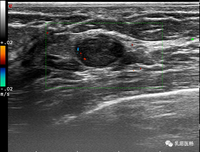

新华社圣彼得堡3月7日电(记者陈畅)俄罗斯研究机构近日训练出一种能够快速识别计算机断层扫描(CT)影像的人工智能,可以协助医生诊断早期乳腺癌。

据塔斯社报道,俄罗斯圣彼得堡国立电子技术大学与阿尔马佐夫国家医学研究中心共同开发了一款医疗诊断辅助软件系统,其核心是神经网络这种人工智能技术。经过训练的神经网络能够自动处理上传至服务器的患者CT影像,标记出具有肿瘤特征的区域。标记后的影像会被发送给医生,由医生作出最终诊断。

研究人员表示,过去解读一张CT影像通常需要一天,而这项技术的影像分析过程仅需几分钟,还可将临床误诊的概率降低约20%。

研究人员援引俄罗斯卫生部国家放射医学研究中心的数据表示,俄罗斯每年有4000至7000人因乳腺癌死亡,较高的死亡率与疾病发现较晚相关。因此,这项新技术有望帮助降低乳腺癌死亡率。